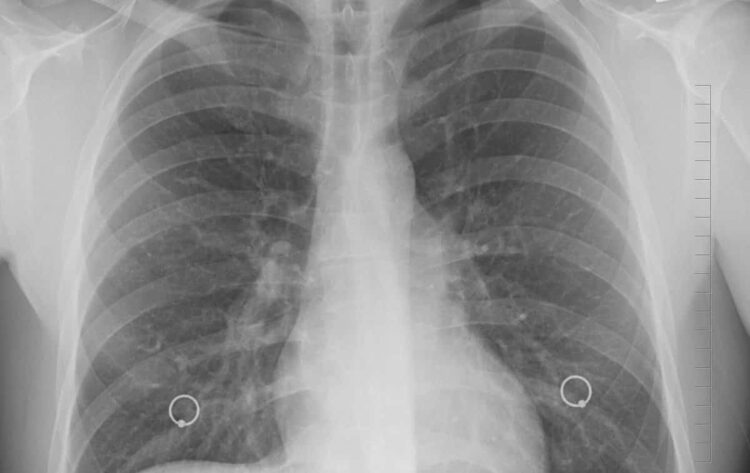

Milano – Presentati allo European Lung Cancer Congress (ELCC) 2025 i nuovi risultati dello studio di fase 3 MARIPOSA per il trattamento con amivantamab più lazertinib di pazienti con carcinoma polmonare non a piccole cellule (NSCLC) localmente avanzato o metastatico con delezioni dell’esone 19 (ex19del) del recettore o mutazioni di sostituzione L858R del fattore di crescita epidermica (EGFR). In particolare, i dati hanno mostrato che la combinazione ha prolungato significativamente la sopravvivenza globale (OS) rispetto a osimertinib.1 Secondo le proiezioni, la sopravvivenza globale mediana, che non è stata ancora raggiunta, potrebbe essere di quattro* anni rispetto ai tre osservati con osimertinib.1 Amivantamab più lazertinib è attualmente approvato nell’Unione Europea per il trattamento in prima linea di pazienti con NSCLC avanzato con mutazione dell’EGFR.2

Lo studio MARIPOSA è il primo studio a mostrare un miglioramento della sopravvivenza globale statisticamente significativo e clinicamente rilevante rispetto allo standard di cura, osimertinib.1 Questo parametro, a differenza della sopravvivenza libera da progressione (PFS) che considera il tempo in cui un trattamento impedisce al tumore di progredire, aiuta a comprendere l’impatto che questo potrebbe avere sulla prospettiva di vita dall’inizio del trattamento.3,4,5